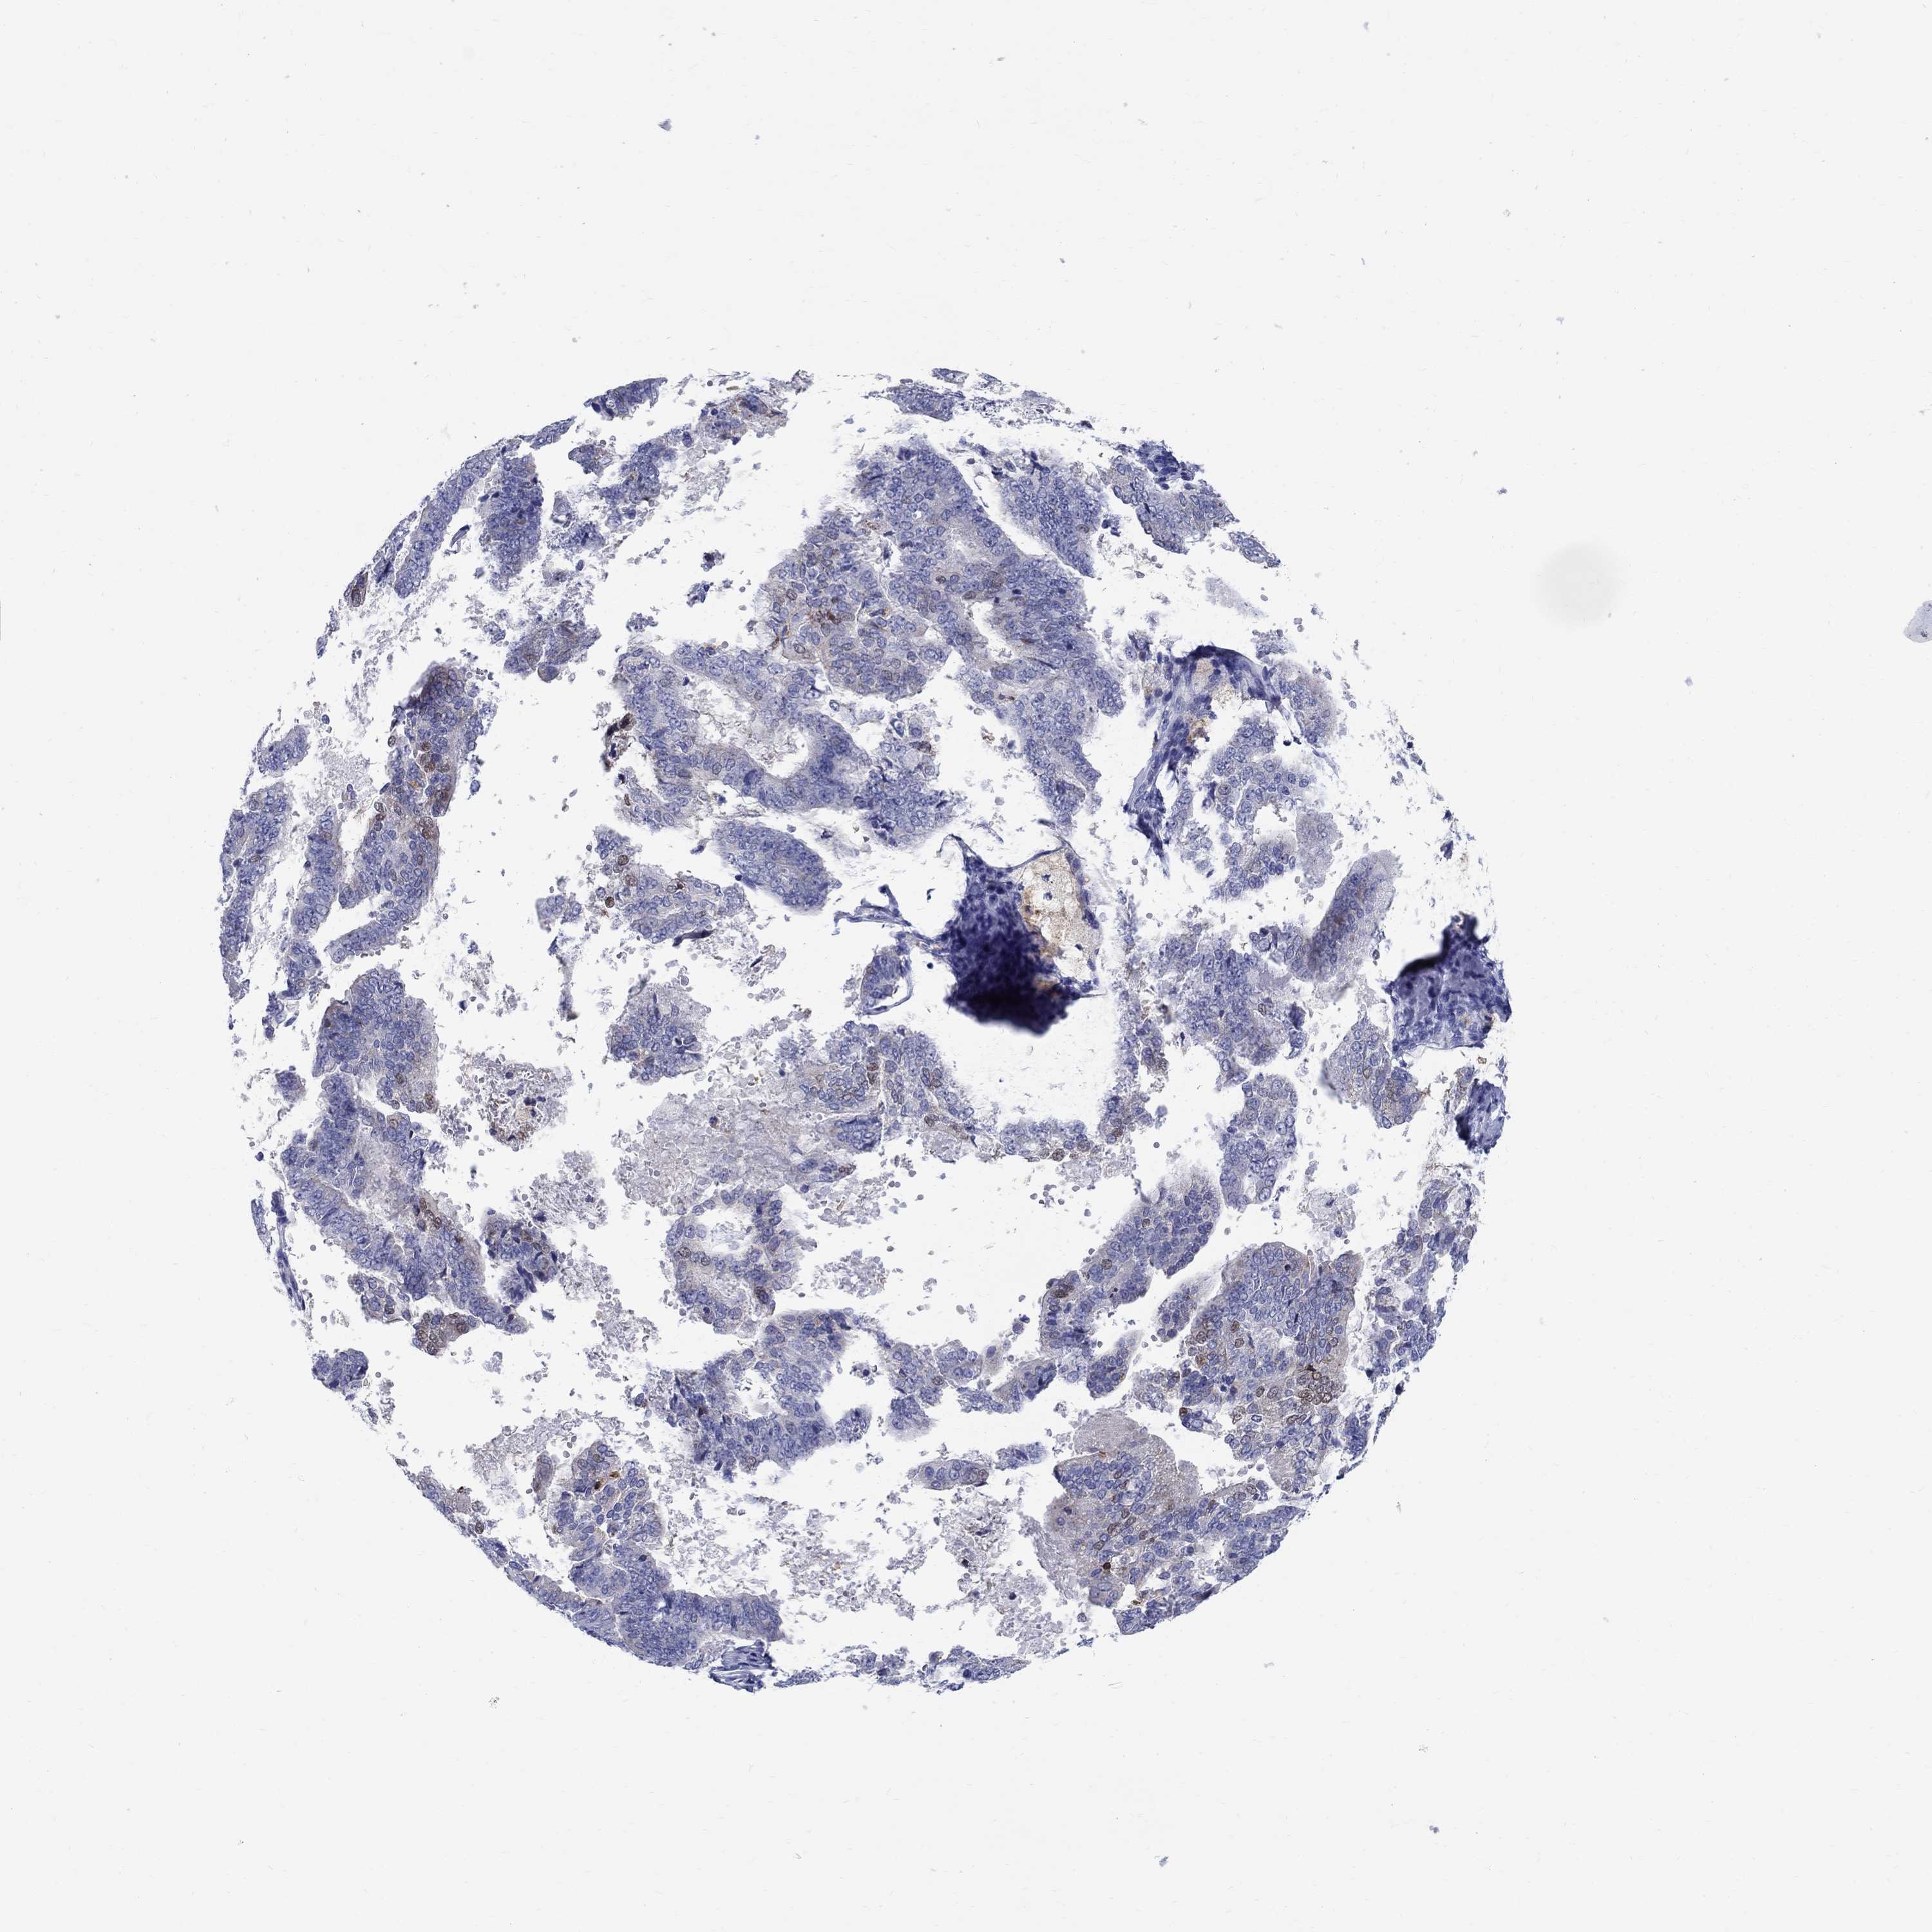

ENDOMETRIAL CANCER - Protein expressioni

A mouse-over function shows sample information and annotation data. Click on an image to view it in a full screen mode. Samples can be filtered based on level of antibody staining by selecting one or several of the following categories: high, medium, low and not detected. The assay and annotation is described here.

Note that samples used for immunohistochemistry by the Human Protein Atlas do not correspond to samples in the TCGA dataset.

Antibody stainingi

Antibody staining in the annotated cell types in the current human tissue is reported as not detected, low, medium, or high, based on conventional immunohistochemistry profiling in selected tissues. This score is based on the combination of the staining intensity and fraction of stained cells.

Each image is clickable and will lead to virtual microscopy that enables deeper exploration of all samples and also displays staining intensity scores, fraction scores and subcellular localization as well as patient and tissue information for each sample.

Antibody HPA045725

Antibody CAB079745

Staining

High

Medium

Low

Not detected

Intensity

Strong

Moderate

Weak

Negative

Quantity

>75%

75%-25%

<25%

None

Location

Nuclear

Cytoplasmic/membranous

Cytoplasmic/membranous,nuclear

Adenocarcinoma, NOS